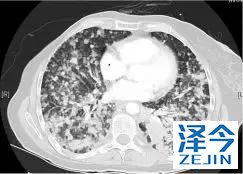

一位77岁的女性患有EPS15-NTRK1 IV期非小细胞肺癌,我们可以看到她的双肺满是病灶,并且出现了肝脏和脑转移,可以说是非常非常晚期了,

肺靶病变达到缓解,我们可以明显的看到前后的图像,病灶明显缩小了,

初始, 2018年6月 3周期 2018年8月